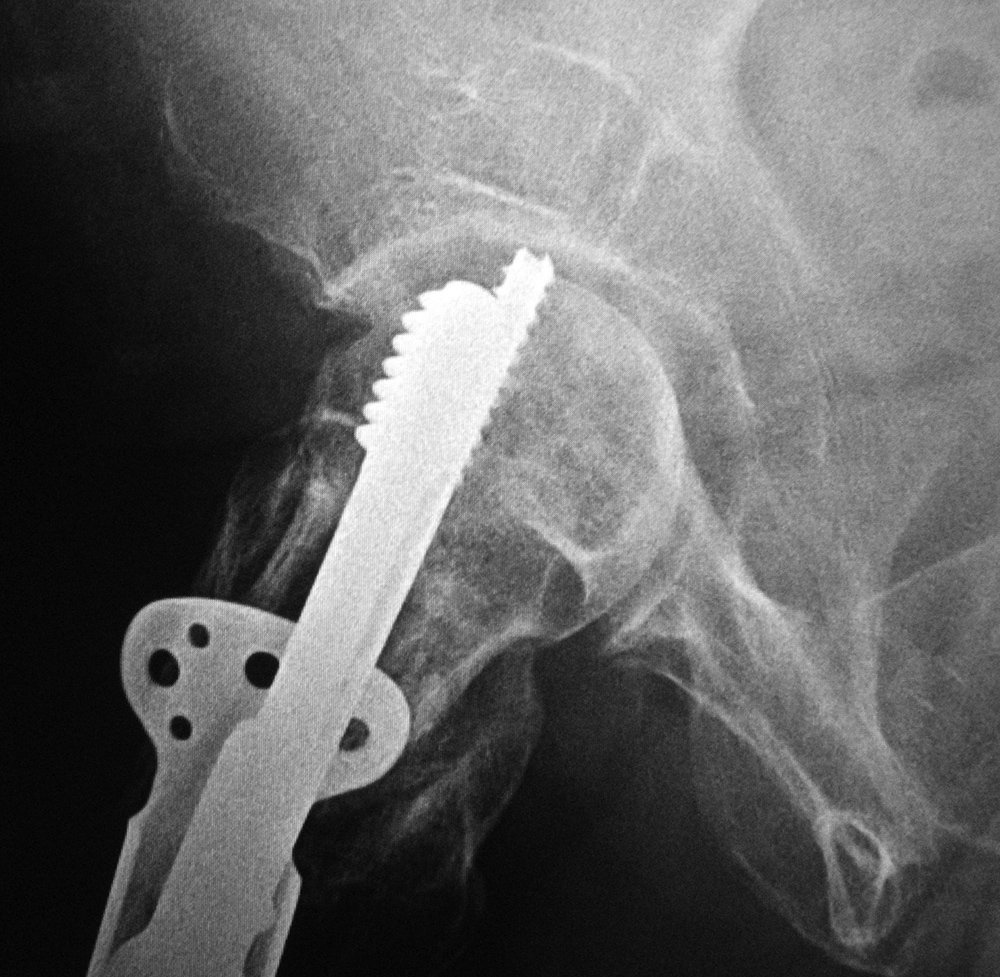

| Fixation screw projecting into right hip joint |

Intraoperative fixation of an intertrochanteric fracture demonstrates a cephalomedullary device with the tip of the cephalic screw positioned too short and very inferior in the neck (very large tip-apex distance). |

Subsequent fracture fixation failure observed as the head and neck segment of the femur flexed 90 degrees with cut-out of the screw approaching the hip joint. |